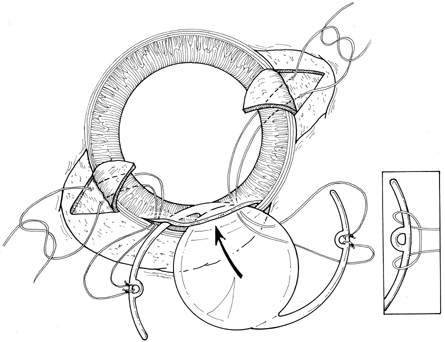

With lens removal, attention should first be paid to any prolapsed or incarcerated tissue. This should be repositioned or excised, and the corneal laceration should be sutured and the anterior chamber re-formed as described. The nature of the injury will suggest the surgical technique used for lens removal. If the lens capsule remains intact, standard phacoemulsification or extracapsular cataract extraction may be performed, making every effort to preserve the integrity of the posterior capsule. In children and young adults, a soft cataractous lens may be removed through a small incision using manual or automated aspiration. When extracting the nucleus in the patient post-trauma, one should be aware of the possibility of poor zonular support. Should zonular weakness, dialysis, or loss be present, a capsular tension ring (CTR) may be used. Implanting a CTR may decrease intraoperative zonule dehiscence, subluxation of the capsular bag, and posterior capsular rupture. A CTR inserted before phacoemulsification will permit support of the capsular bag, reestablishing its contour and protecting it from getting aspirated.14 The CTR (Morcher; distributed by FCI Ophthalmics, Inc., Marshfield Hills, MA) comes in three sizes and is usually inserted after capsulorrhexis and hydrodissection. For insertion, it is best to enter the bag in the area of greatest zonular weakness, thus placing stress on the stronger zonules, 180 degrees away. The ring is dialed into the bag using a second instrument (e.g., Y-hook) (Fig. 14). Alternatively, a CTR injector may be used.